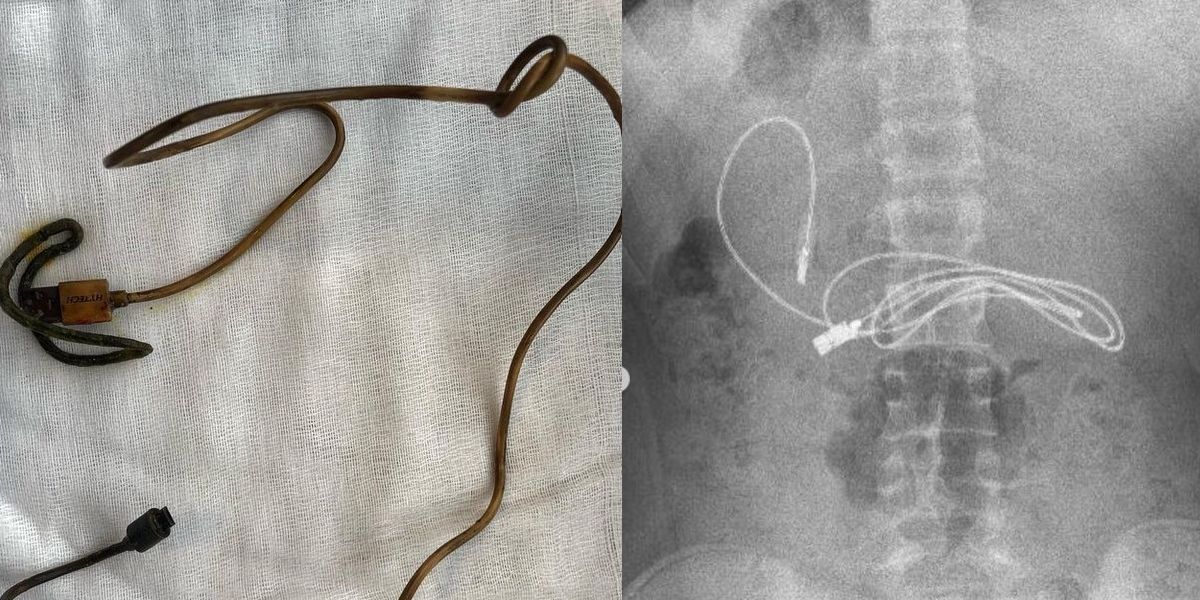

Neben dem Ladekabel hatte der Bub auch noch ein Haarband geschluckt. Warum, ist unbekannt.